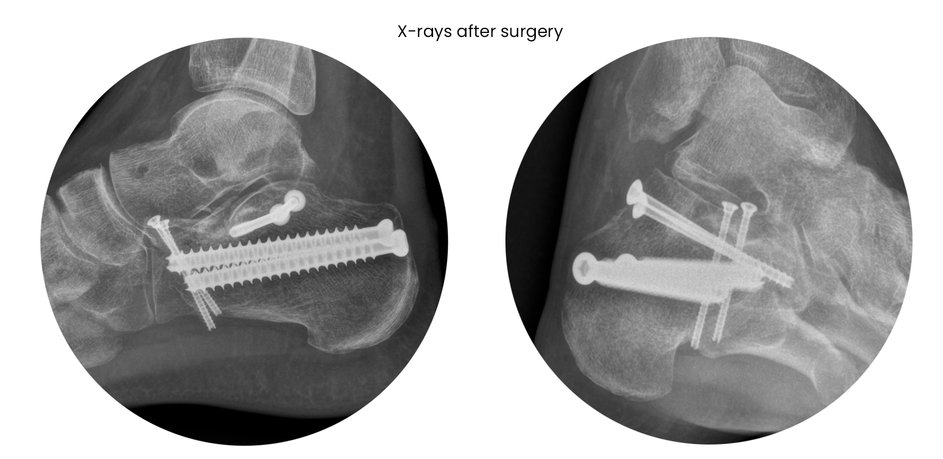

case 18ZJ, 23 years old, female, fall from horse, "atypical fracture" surgery after 2 days